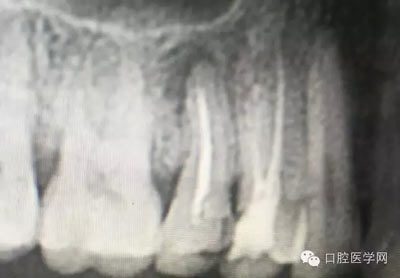

這是一例外院樹脂修復后十個月出現(xiàn)牙髓炎癥狀的患者。遇到這樣子的患者大家會怎么做,證明選擇,還有就是可做可不做治療的如何去平衡。

根管治療,我們在大學的時候就學習的東西,標準就在那里放著,可是很多時候我們熟視無睹,放任我們的想象去做。我們多些重視,多些心思,會好很多,認真對待每顆牙齒。